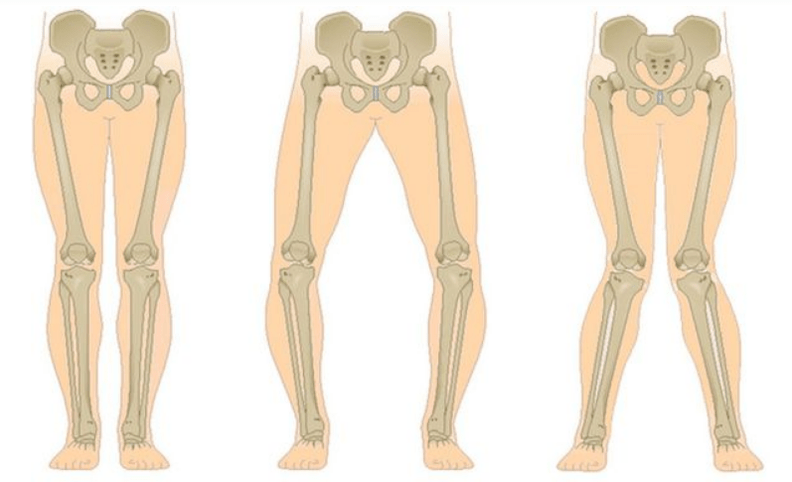

De laatste fase van gonartrose onderscheidt zich door het feit dat de pijn vrijwel constant wordt, waardoor niet alleen angst ontstaat tijdens het lopen, maar ook in rust, en zelfs 's nachts, wanneer patiënten op zoek moeten naar een comfortabele slaaphouding. De beweging is beperkter: het is moeilijk om het been volledig te buigen en te strekken. Het gewricht raakt vervormd en neemt in volume toe. Valgus (X-vormige) of varus (O-vormige) misvorming van de benen wordt vaak waargenomen. De gang wordt onstabiel en waggelt. In ernstige gevallen zijn een wandelstok of krukken nodig.

De meest voorkomende complicatie van fase II en III is tendovaginitis van de adductorspiergroep van de dij. Dit manifesteert zich door pijn langs het binnenoppervlak van het gewricht, die intenser wordt bij beweging. De oorzaak is spieronbalans en vervorming. Bij een langdurige afname van het bewegingsbereik ontstaat contractuur. Bovendien komt synovitis vaak voor.